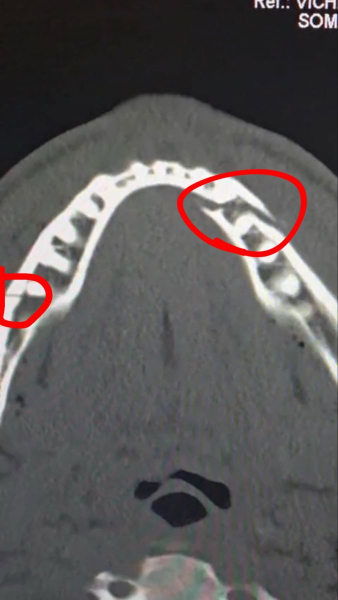

The 28-year-old showman, who drove himself to the hospital, posted a photo on social media from the ward with his 30-year-old brother Logan and an X-ray showing that his jaw was broken in two places.

“Proud brother of a true warrior. They broke his jaw, but they couldn't break his spirit,” Logan Paul wrote.